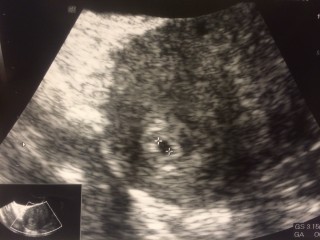

いつもしっかり生理が予定通りにくるのに今回はこない… 妊娠検査薬で陽性が出たので産婦人科へ。 3.9mmの小さいお豆さんが! 先生に言われないと分からないほど。 2週間後の心拍確認♪待ち遠しいです(*'▽') 結婚2年目で授かった命、旦那と大事にしていきます。

4週後半で受診。見えなくてもおかしくない頃だけど、見えてよかったね。と先生に言われました。 子宮外妊娠でなかったことが確認できて一安心。 まだ、袋だけしか確認できませんが、いとおしくてたまらないです。

ベビ待ち6ヶ月で待望の陽性反応&胎嚢確認です!! 胎嚢5mmと週数にしては小さいようなので とっても不安ですが赤ちゃんを信じようと思います! 来週胚芽確認出来ますように(>_<)♪